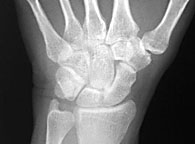

| Posteroanterior (PA) view |

Views of the wrist